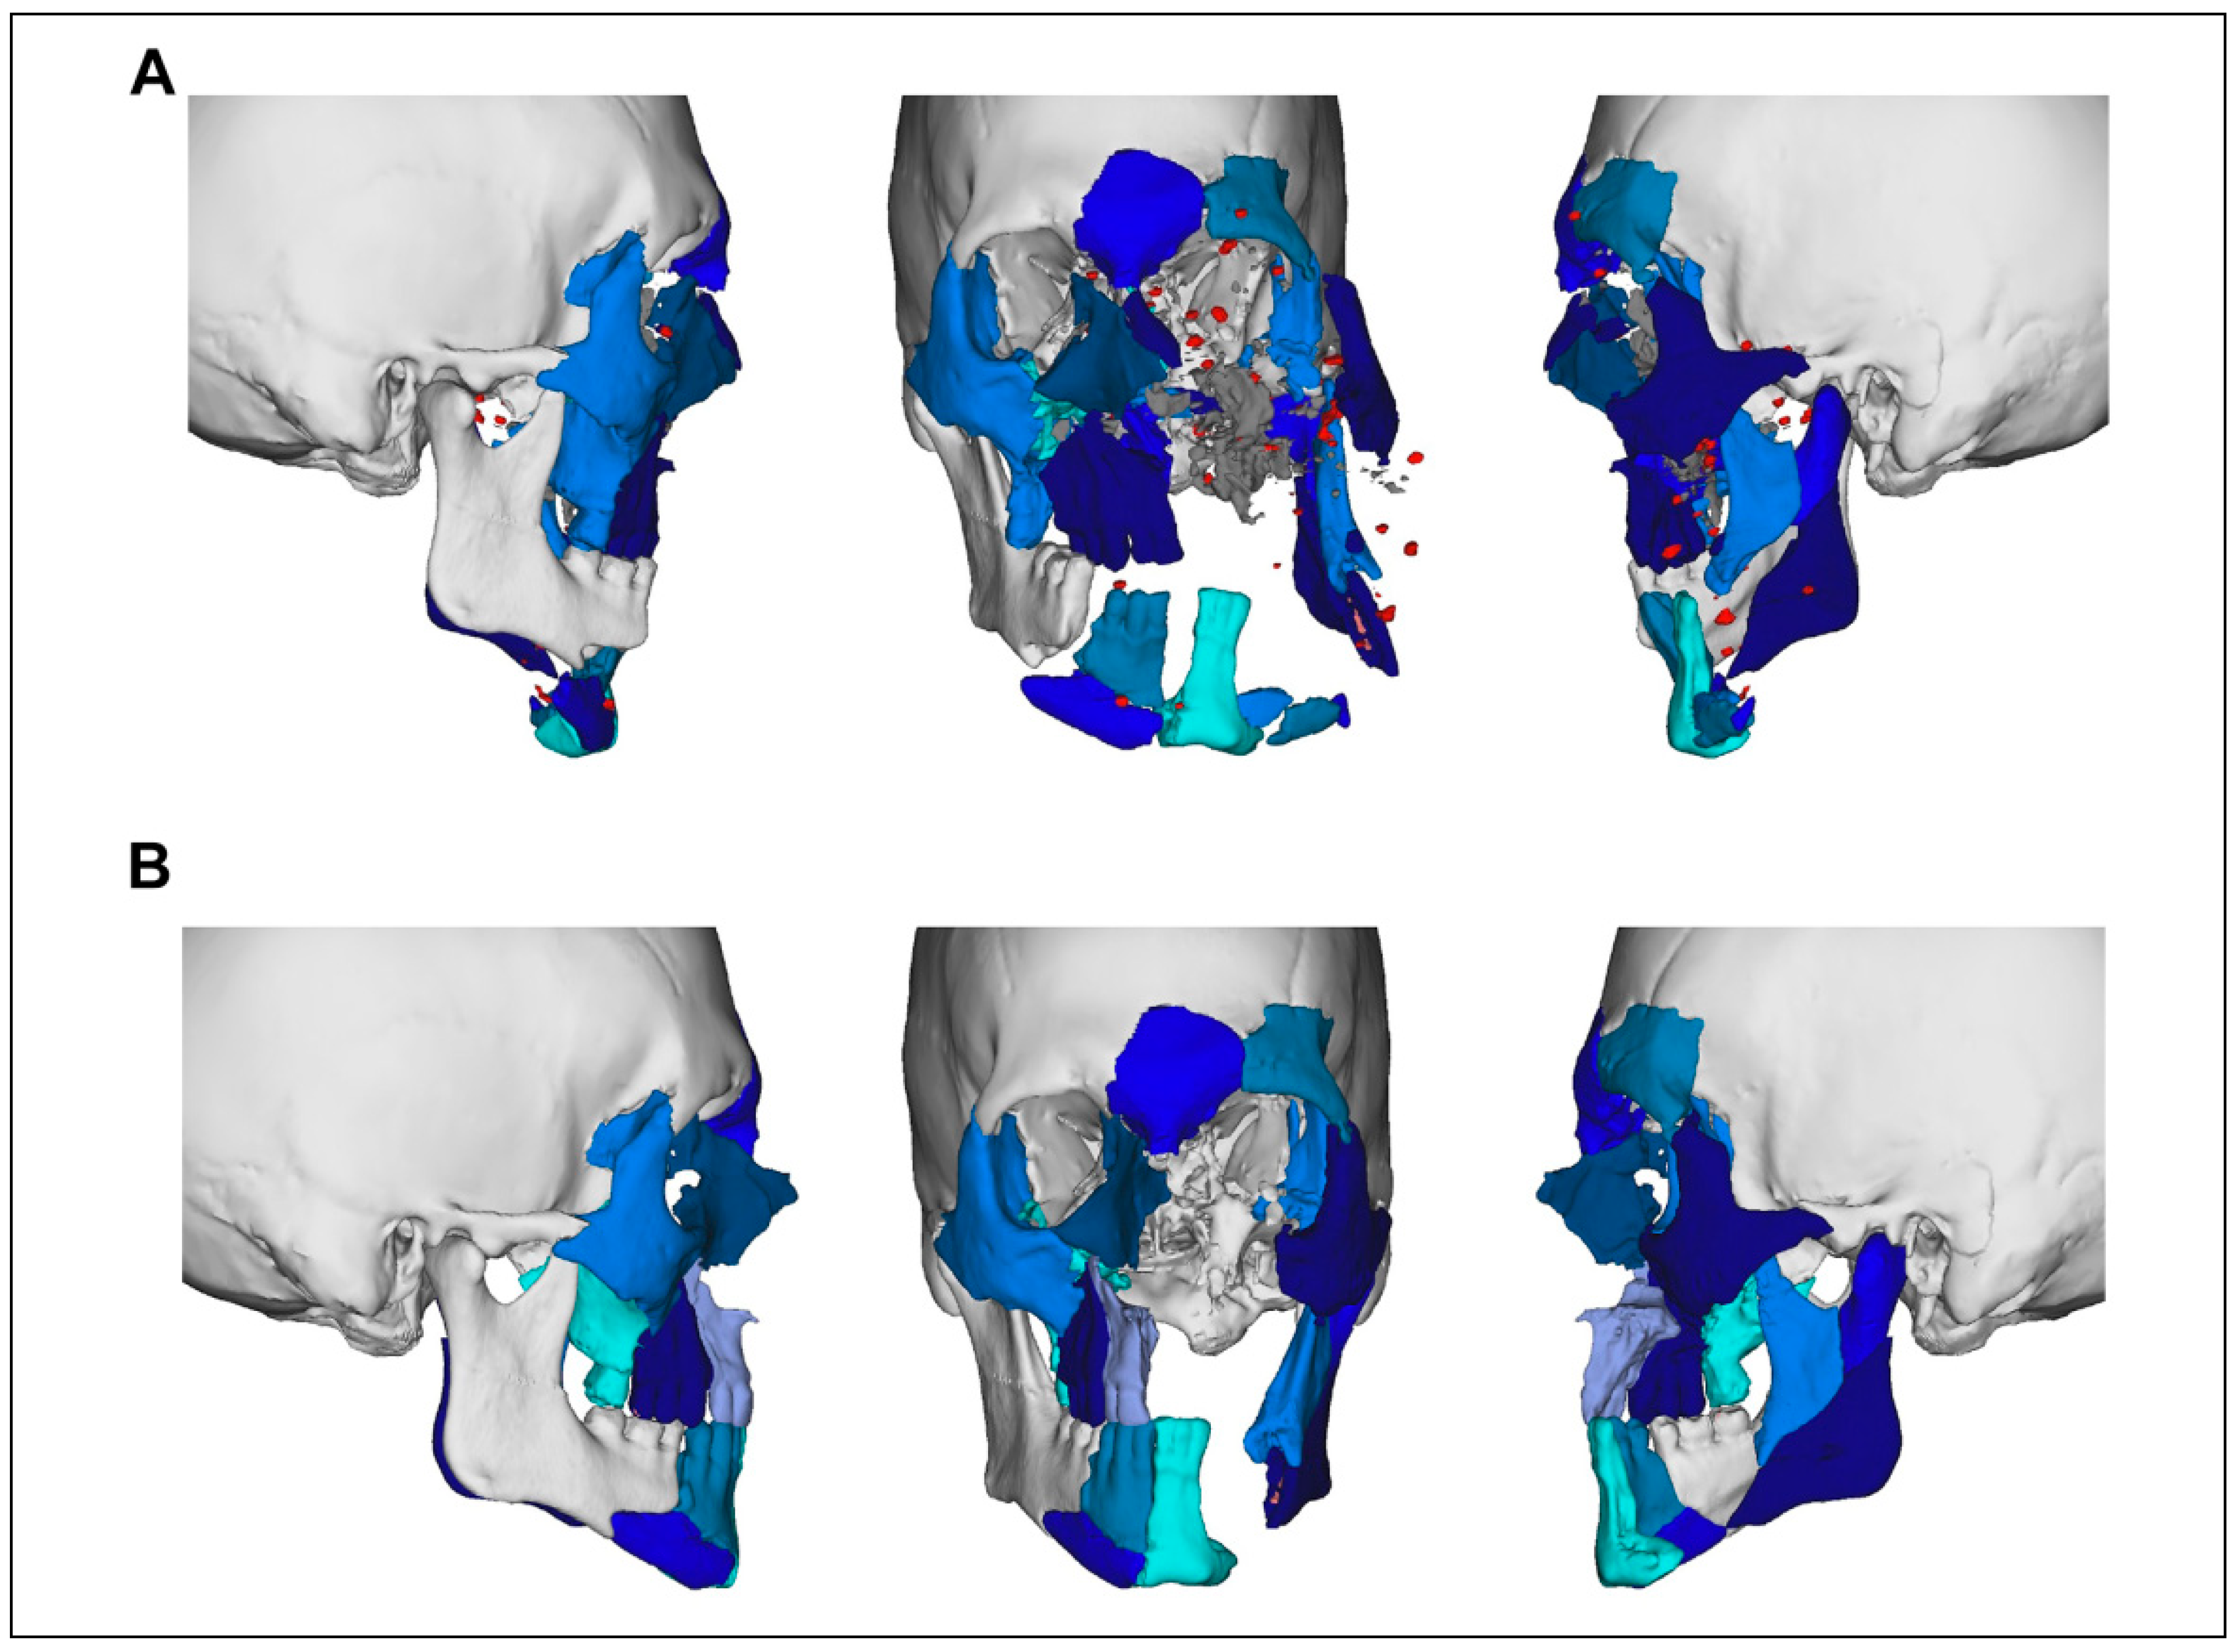

Case Series

Case Presentations